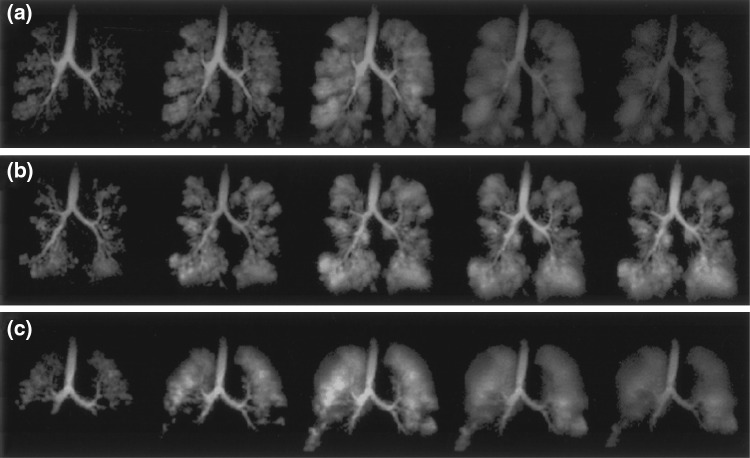

Fig. 12.

Dynamic spiral readout hyperpolarized 3He lung images of patients demonstrating variations in lung ventilation with a severe asthma, b cystic fibrosis, c emphysema secondary to α-1 antitrypsin deficiency.

Reproduced with permission from Salerno et al. [11]